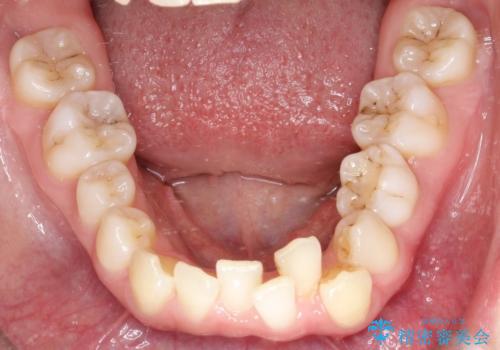

【インビザライン】 前歯の反対咬合を治したい

左下5番は先天性欠損のため乳歯は抜歯しインプラントにて欠損補綴しています。